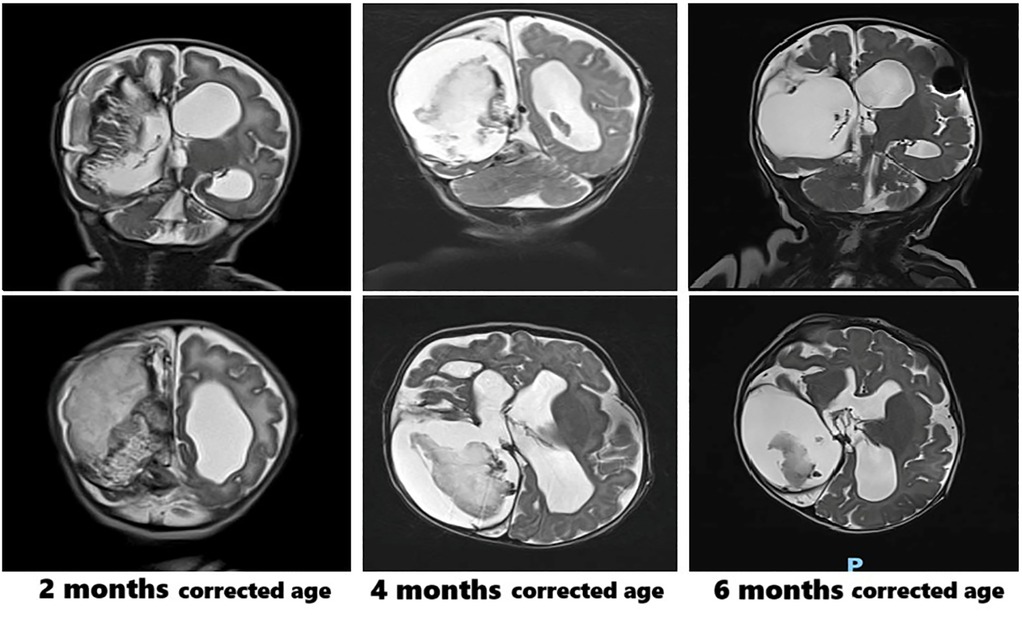

ABSTRACT Background: Congenital syphilis (CS) remains a global public health concern, with rising incidence even in high-income countries. In Italy, a higher risk has been reported among primigravidae and younger mothers with late or missed prenatal screening. While neurological involvement in CS is well known, it is rarely reported in preterm infants, where it may be severe and atypical. Case Presentation A male preterm infant, delivered at 32 weeks via emergency cesarean due to abnormal fetal monitoring and breech position, was admitted to our NICU with intraventricular hemorrhage, midline shift, and hydrocephalus, requiring neurosurgery. He later developed a metaphyseal bone lesion; Staphylococcus aureus was found in blood cultures. Despite antibiotics, persistent thrombocytopenia and infectious symptoms led to further testing, revealing congenital syphilis with neurological involvement and osteomyelitis and osteochondritis of the distal ulna and radio from an undetected maternal treponemal infection during pregnancy. Penicillin therapy produced slow recovery, but the newborn developed epilepsy and spastic tetraplegia by 24 months. Genetic and metabolic tests were negative. Literature review rarely shows similar CS cases, especially in preterm infants. Conclusion: This case highlights the relevance of universal maternal syphilis screening and early neonatal evaluation. Maternal Treponema pallidum infection during pregnancy can result in preterm birth and may be associated with neurological complications, such as hemorrhages, seizures, and motor impairment, which can require multidisciplinary management and long-term follow-up.